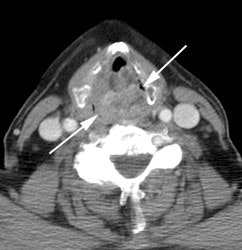

Large laryngeal cancer: The patient shown below had a large laryngeal cancer (white arrows). The PET exam demonstrated very prominent uptake within the mass, but no evidence of metastatic disease.

Large laryngeal cancer: The patient shown below had a large laryngeal cancer (white arrows). The PET exam demonstrated very prominent uptake within the mass, but no evidence of metastatic disease. |